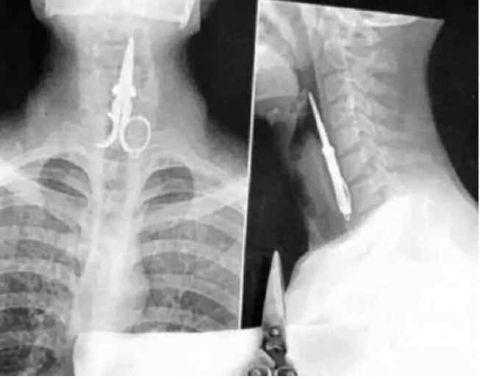

酒吧里面打架被人插得刀子

又是打架时候干的,不过这人现在康复了